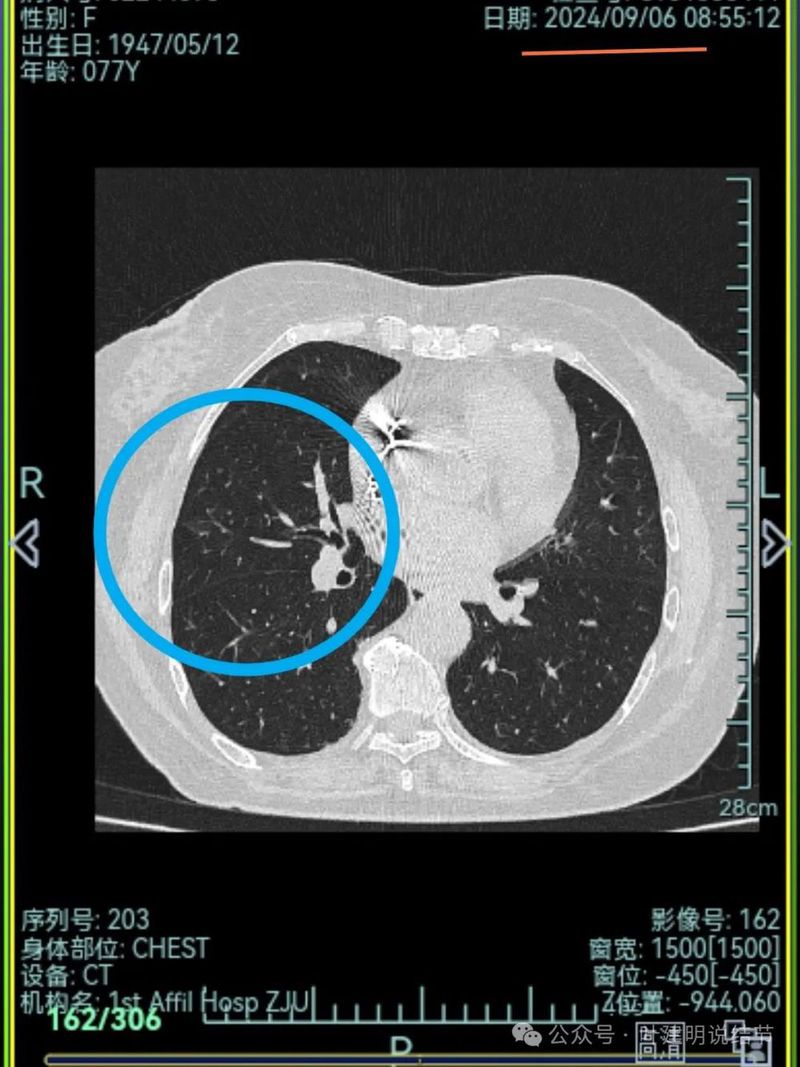

再来看2024年9月时的关键影像:

右上后段灶病灶不单没有好转,灶内密度是有增加进展的!

有明显血管进入,表面分叶,边缘不平,整体轮廓清。

边缘毛刺、表面不平、灶内偏实性成分、分叶明显,整体轮廓与瘤肺边界较为清楚。

灶内细支气管扩张、边缘毛刺较为锐利、有明显磨玻璃成分,磨玻璃成分的瘤肺边界清楚,病灶分叶明显。

灶内密度杂乱不均,内有小空泡征,表面不平。

灶内血管增粗穿行、磨玻璃成分明显,轮廓较清。

血管进入,磨玻璃成分,支气管扩张,边缘不平。

典型混合密度病灶,中间部分密度高偏实性,外围部分磨玻璃密度,两者之间交错存在,说明偏实性部分有侵袭性。磨玻璃成分与正常肺组织之间界限清楚,表面分叶,部分边缘毛刺,整体轮廓清。是非常符合恶性的影像表现。

灶内磨玻璃成分明显,并有异常增粗血管僵硬穿行于病灶内,支气管有扩张通气征,瘤肺边界清楚,实性成分明显。